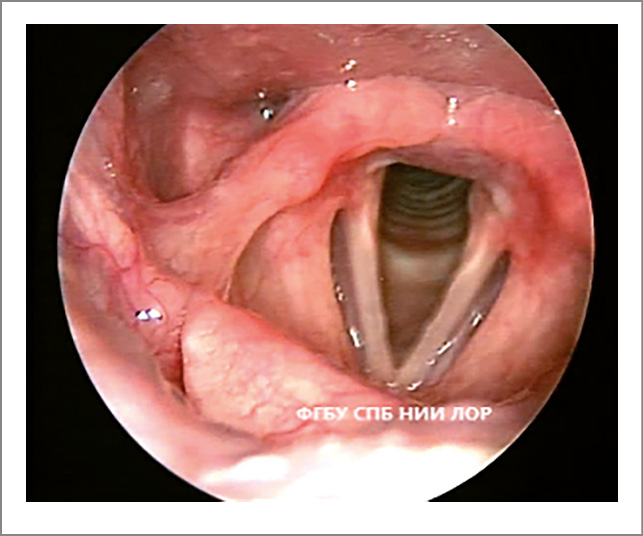

- Фонационная щель пациентов с функциональной дисфонией не соответствует форме фонационной щели здоровых людей. Изменение формы фонационной щели – основной признак гипотонуса голосовых складок. Сниженный тонус мышц гортани проявляется овальной, широкой линейной или треугольной фонационной щелью. Если у пациентов с функциональной дисфонией форма фонационной щели напоминает овал, то это свидетельствует о преимущественном снижении тонуса голосовых мышц (рис. 1). При снижении тонуса межчерпаловидных мышц фонационная щель имеет вид треугольника с верхушкой в передней комиссуре и основанием в межчерпаловидной области (рис. 2).

Рис. 1. Функциональная дисфония по гипотонусному типу (фонация): овальная щель.

Рис. 2. Функциональная дисфония по гипотонусному типу (фонация): треугольная щель.